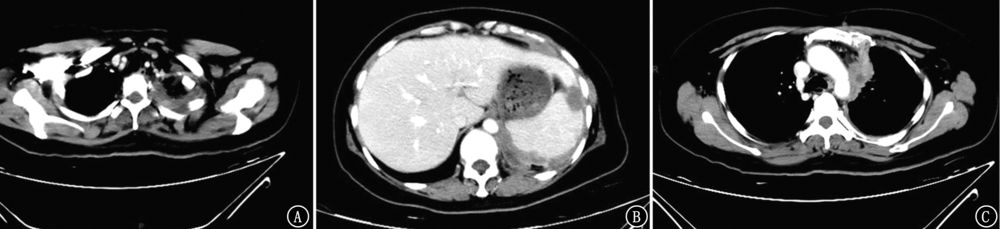

宫颈癌的主要转移途径是直接蔓延、淋巴转移和血行转移,较常见的远处转移部位为肺、肝、骨骼等,宫颈癌胸膜转移报道较少,现报道1例宫颈癌发生胸膜转移并快速进展导致死亡的病例,以提高对少见部位转移的宫颈癌的重视。